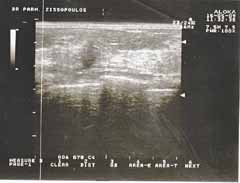

Η κλινικο-υπερηχογραφική διερεύνηση του μαστού είναι μία ακίνδυνη και πολύ αποτελεσματική μέθοδος εντόπισης εστιακών ευρημάτων.

Οι απεικονίσεις των περιστατικών που επιδεικνύονται παρακάτω, έγιναν με κυρτές κεφαλές 3,5 και 5 ΜΗΖ, προκειμένου να φανεί, ότι και με τον εξοπλισμό αυτό, που σιγά-σιγά διαθέτουν όλο και περισσότερα ιατρεία, είμαστε σε θέση να έχουμε ικανοποιητικά αποτελέσματα.

Oι τελευταίες 4 απεικονίσεις έγιναν με ειδικό για μαστό ηχοβολέα linear, εναλλασσομένης συχνότητος 7,5-10ΜΗΖ.